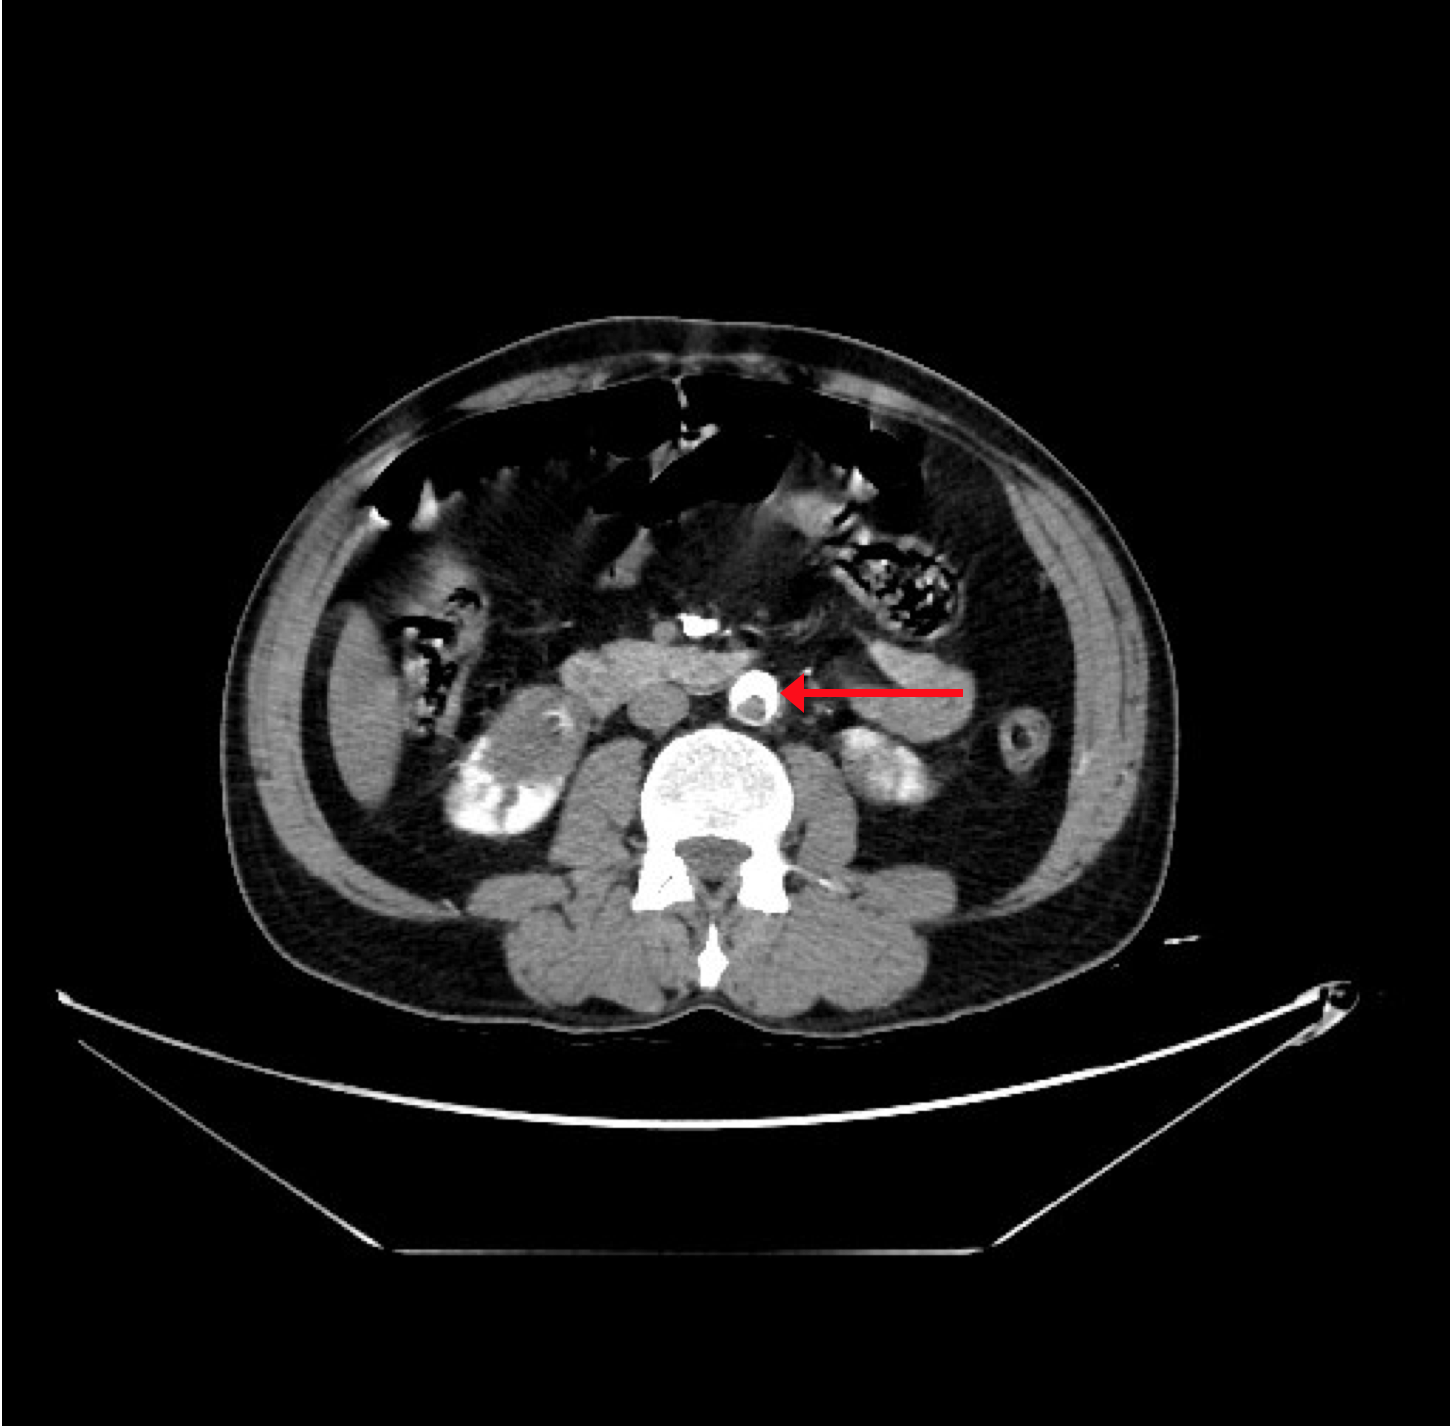

The CT angiogram and CT chest aortogram revealed a hypodense filling defect in the aorta below the level of the renal arteries causing partial occlusion of the aorta (Figure 2). There was complete occlusion of the left common iliac artery just after bifurcation of aorta extending up to the common femoral artery (Figure 3). There was good contrast uptake in right common iliac artery, femoral artery, superficial femoral artery up to the popliteal artery then the abrupt cut off of right popliteal artery present with no contrast filling seen in the distal arteries (Figure 4 and 5). Additionally, multiple bilateral wedge shaped infarcts seen in both the kidneys and the spleen (Figures 6). Chest x-ray was normal.

Figure 2: CT aortogram revealing filling defect in the infra-renal aorta.

Figure 5: CT Aortogram revealing multiple infarcts in the both kidneys in coronal section.

Figure 6:CT Aortogram revealing multiple infarcts in the spleen in transverse section.